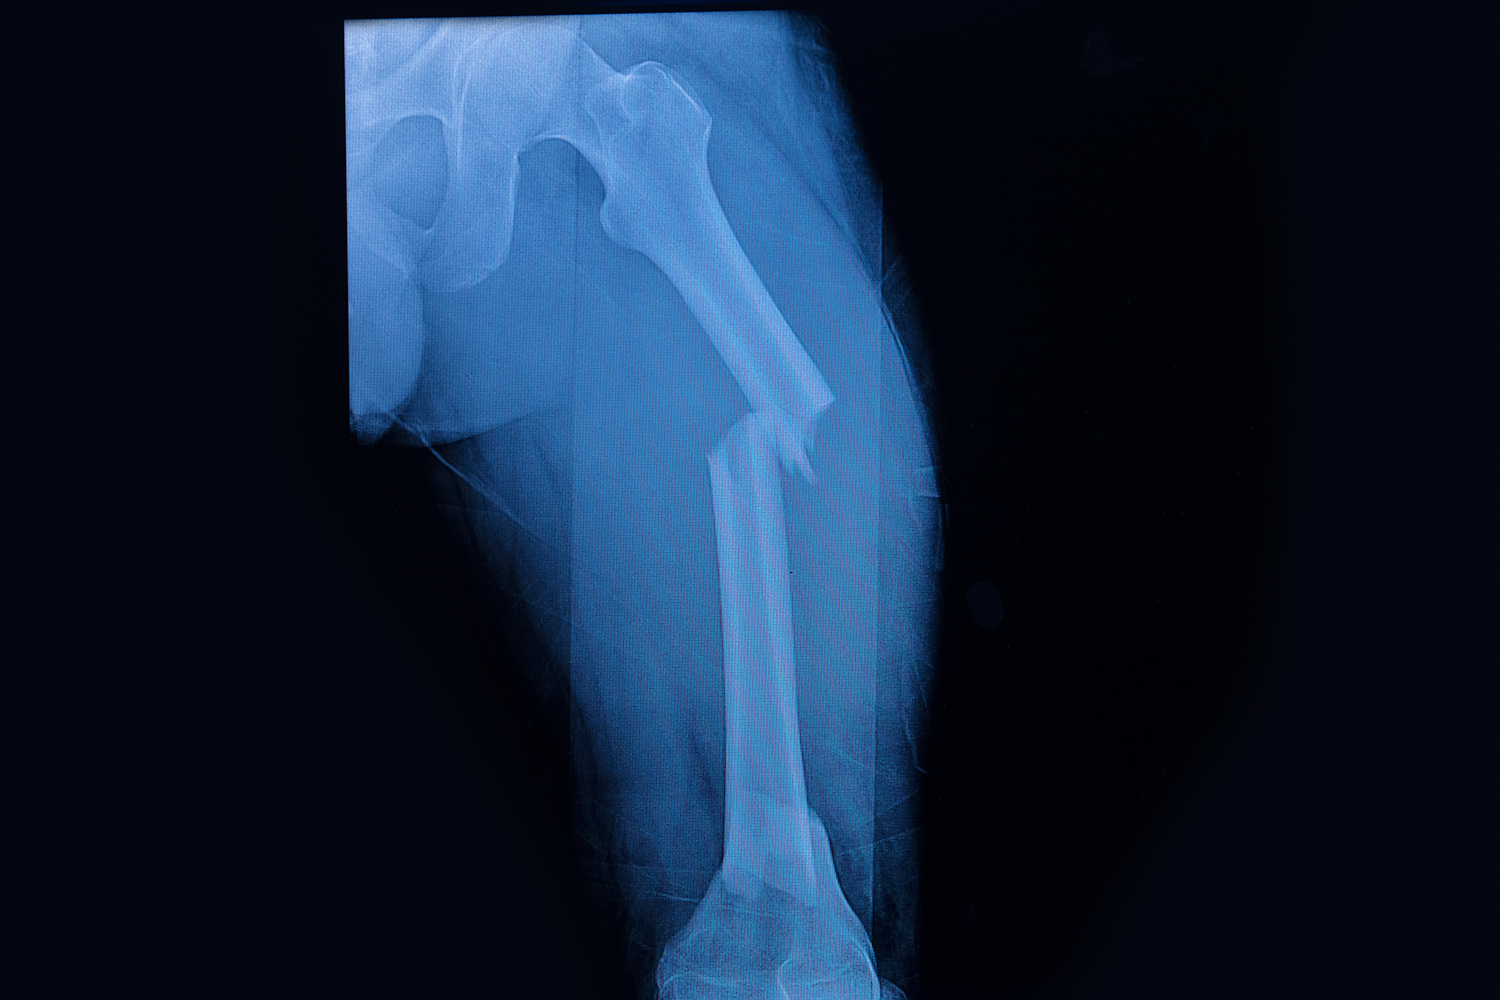

Concern has grown among patients and clinicians that bisphosphonates, the most common treatment for osteoporosis, may be related to development of atypical femoral fractures (AFF). In fact, bisphosphonate use has declined more than 30 percent since 2006-2007 because of the uncertainty of risk versus benefits.

Bauer and his colleagues expect to describe the rates of radiographically confirmed AFF by age, gender and duration of bisphosphonate use. They also want to determine the independent effect of bisphosphonates by duration of use and cumulative dose on AFF, as well as the impact of other factors like severity of osteoporosis, other medical conditions and other medications. A third goal is to determine if AFF risk declines after discontinuation of bisphosphonates and patient and treatment characteristics that influence risk after discontinuation.